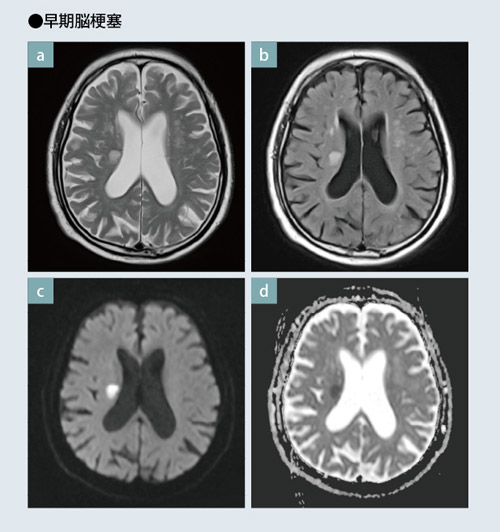

頭頸部のCT・MRI 第3版 | 尾尻博也, 酒井 修 |本 | 通販 | Amazon。MEDSi)株式会社 メディカル・サイエンス・インターナショナル。頭頚部 CT : 正常解剖学 | e-Anatomy。フライドガーリック粒 にんにく ニンニク 500g 1袋。頭部 | ページ 2。頸部リンパ節のレベルシステムとMRI横断像の関係。頭部CT検査 | オリエンタル蒲郡健診センター。Philips - dStream Sentinelle Breast 16ch HCNMRF465 MR coil。。頭頚部 CT: 正常解剖学 | e-Anatomy。頭頚部 CT: 正常解剖学 | e-Anatomy。咽頭扁桃 - e-Anatomy - IMAIOS。なんせい動物病院/CT・MRIセンター | コラム。MRI検査 | 埼玉メディカルセンター | 地域医療機能推進機構。裁断済み、一部マーカー引いてあります。